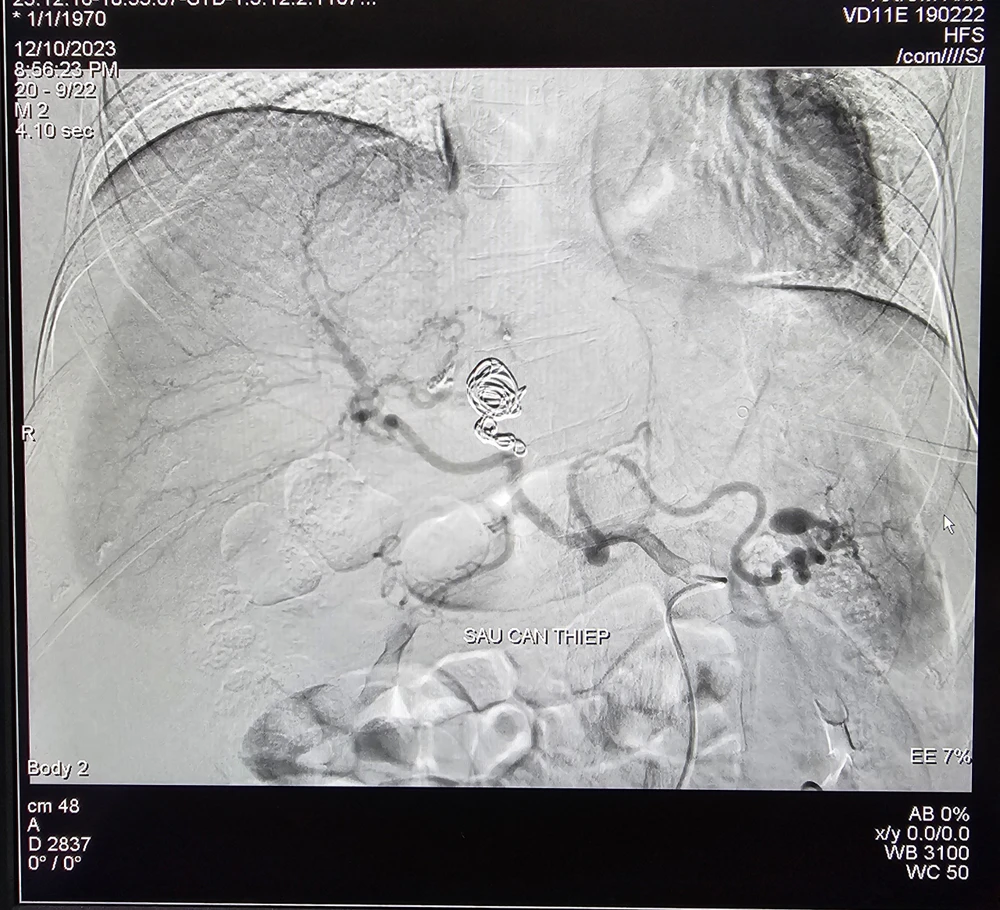

benh-hiem-gap-sau-can-thiep.jpg

Động mạch gan của bệnh nhân sau khi được can thiệp

Tiến hành can thiệp, các bác thực hiện chọn lọc vào nhánh động mạch gan trái có tổn thương, xác định vị trí và tiến hành thả 03 vòng xoắn kim loại vào ổ giả phình, tiếp tục bơm hỗn hợp keo sinh học gây bít tắc hoàn toàn túi phình .

Sau 90 phút can thiệp, bệnh nhân ổn định được chuyển khu hậu phẫu theo dõi và hiện bệnh nhân tỉnh, tiếp xúc tốt, niêm hồng, hết đau bụng, sinh tồn ổn định, đang được theo dõi và điều trị.